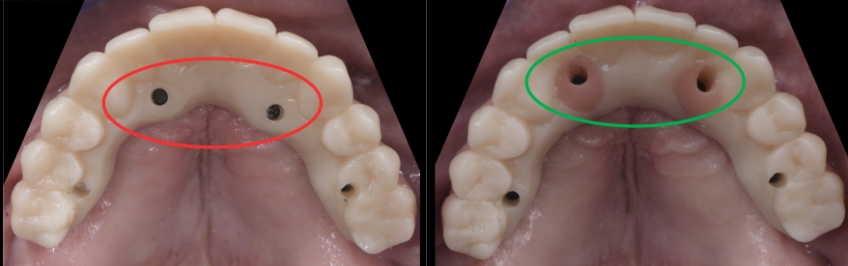

Usually, straight SRA abutments are used with anterior implants when they are parallel. Still, it is not uncommon for the restorative dentist to realize during the prosthetic phase of treatment that the position of the screw access hole could be optimized by changing the angulation of the SRA abutments. Ideally, the treating team aims to have the access holes coming out of the cingulum in anterior implants and the center of the occlusal area in posterior implants.

Suppose we decide to alter the angulation of the SRA abutments. In that case, we can position the access hole more anteriorly, thus increasing the palatal thickness and improving the biomechanics and hygiene access.

In this visual essay, we have outlined the steps in the fabrication of a maxillary full arch implant-supported prosthesis solution where the SRA abutment needs to be changed because the orientation of the screw access hole in the provisional restorations seems too palatal from an ideal position, thereby underlining the importance of analyzing these aspects during the provisional phase and correcting the angulation of them to provide a more ideal design and increase the long term predictability of the prosthetics.